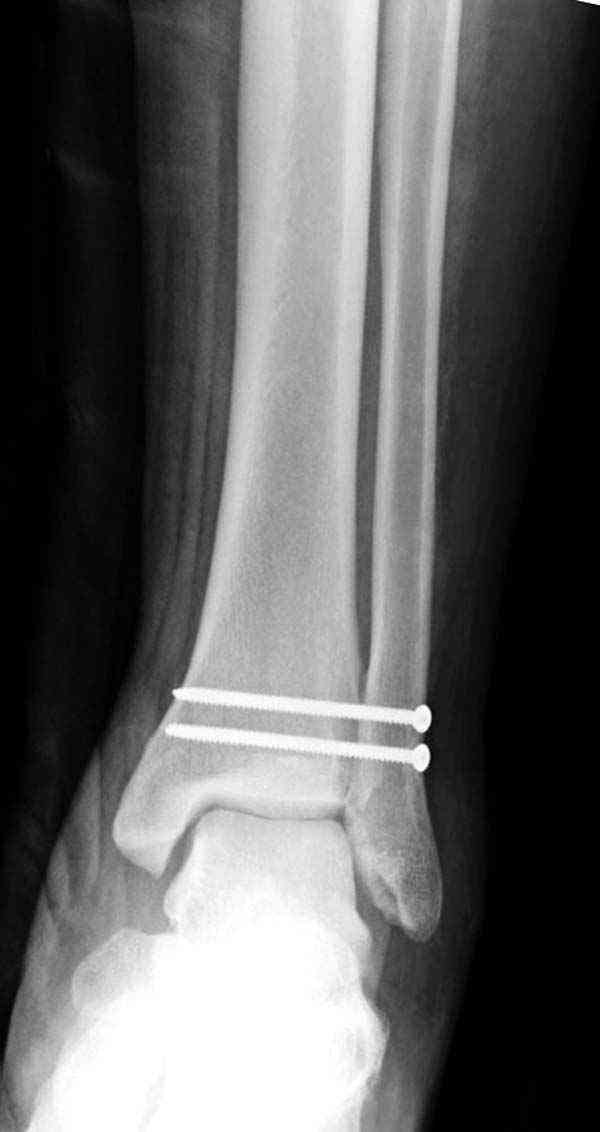

Случай прошлого года:пациентка-молодая ,крупная женщина ,30лет.Травма в начале апреля 2009г-пронационный перелом лодыжек с подвывихом стопы.Ко мне обратилась через 35 дней,прооперирована 22.05.2009г.Внутренняя лодыжка фиксирована по Веберу,наружная реконструктивной пластиной с наложением болта-стяжки.Иммобилизация "сапожок" в течении месяца,затем пригипсовано "стремя".Гипс снят 10.07.2009г

Достаточно быстрое восстановление функции.В октябре 2009г-почувствовала боль,в области рубца над гайкой открылся свищ.На Р-граммах-консолидация переломов и смещение гайки по стяжке.10.11.2009г-конструкции удалены,санация,заживление ран.В настоящее время пациентку ничего не беспокоит.На операции-раскручивание гайки-болталась на конце стяжки.Вопросы:какой механизм раскручивания и что я неправильно сделал?Свои версии:1)в области синдесмоза успела образоваться рубцовая ткань,которая при движении в суставе"пружинила",поскольку голеностопный сустав является спиральным, то и биомеханика подобна кривошипному механизму.2)Реконструктивная пластина не "реконструировалась" по форме лодыжки.Наложил,как есть.То есть подпружинивала сама пластина.Ну,это мои догадки.Что нужно,чтобы избегать впредь таких,пусть и не "страшных"осложнений:Рассверливать через лодыжку область синдесмоза?Ставить шайбу-гровер?Тщательно моделировать пластину?Прилагаю сравнительные снимки-сразу после операции и перед удалением конструкции.

Визуально никаких вопросов по репозиции не было.Да и на основании чего сомнения,что наружная лодыжка не полностью репонирована или прорезалась проволка ???Я не вижу...Снимок после репозиции справа.